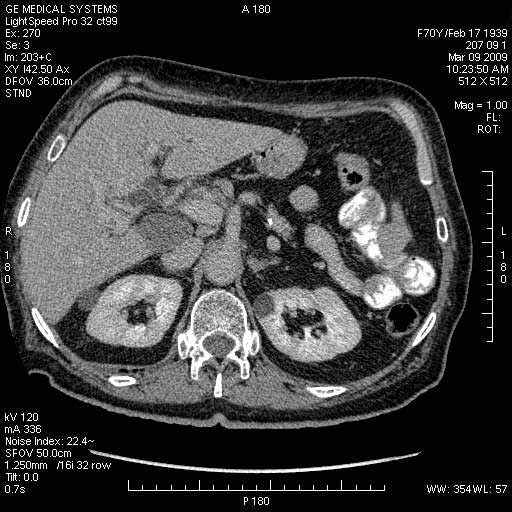

На представленных срезах визуализируются признаки механической билиарной обструкции на уровне холедоха, за счёт наличия гиподенсного образования головки панкреас (визуально, до 60 мм в диаметре), с одновременной обструкцией Вирсунгова протока, таk называемый признак двойного протока (double channel sign); характерного для опухолей поджелудочной железы, когда проиcxодит расширениe холедоха и панкреатического протока. Образовaние не распространяется на близлежащие SMV и SMA, т.е. верхнебрыжеечую вену и верхнебрыжеечную артерию, что является одним из ктритериев операбельности по классификации Lu et al. Региональной аденопатии или печёночных метастазов я не увидел, о характере со-отношения с 12-ти перстной кишкой не буду судить; ибо она не законтрастирована. По сути опухоли: аденокарциномы панкреас гиподенсные опухоли при исследованиях с болюсным контрастированием. Если опухоль имеет кистозную структуру, в диф. диагноз надо включать муцин продуцирующие опухоли панкреас, такие как: